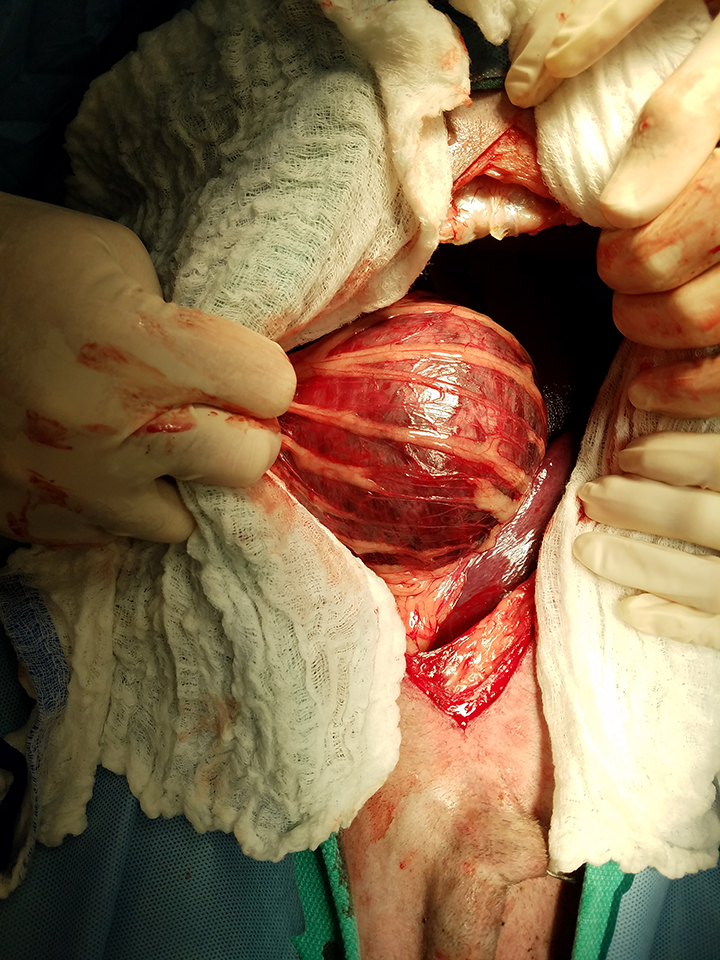

Gastric dilatation volvulus surgery clearance

Gastric dilatation volvulus surgery clearance

Gastric Dilatation and Volvulus Collie Health Foundation

GDV in Dogs Diagnosis Treatment and Management Animal Emergency Australia

Gastric dilatation volvulus surgery clearance

- gastric dilatation volvulus surgery

- gastric dilatation volvulus treatment

- gastric dilation dogs symptoms

- gastric torsion in dogs treatment